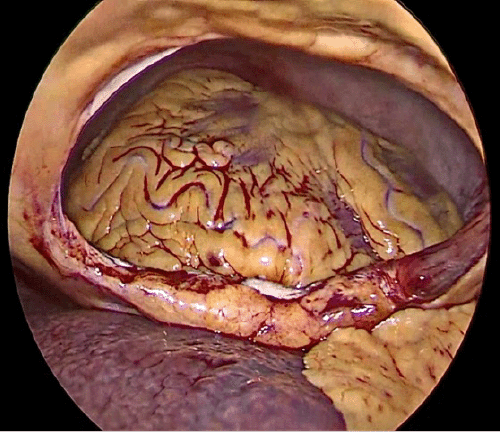

As the patient was hemodynamically stable and there was no internal bleeding, we decided to proceed with laparoscopic surgery with the possibility of conversion at any time if the patient became hypotensive. The patient signed the consent form and underwent surgery after proper preparation. Following induction of anesthesia, bilateral 28-Fr chest tubes (Polymed Medical Devices, Haryana, India) were inserted; 200 mL (0.2 × 10-3 m3) of blood was drained from the left tube, while the right tube did not have any observable output. The patient was stable enough to proceed to laparoscopic surgery. The abdominal cavity was approached from a supraumbilical incision using the open Hasson technique. Two 5-mm trocars (Covidien, Mansfield, MA, USA) were inserted from the left and right subcostal areas under laparoscopic visualization. Upon entering the abdominal cavity, we observed a central diaphragmatic defect communicating with the pericardial space. The heart was seen beating through the 8 cm diaphragmatic defect, with no perceptible damage or free blood in the abdomen (Figure 4). There was a small injury on the edge of the left lobe of the liver without any active bleeding, the stomach was mildly distended with no perceptible injury, there was no splenic injury, and the bowel and mesentery looked normal and healthy. The defect was closed by running a 2-0 tension-free, nonabsorbable suture; three interrupted stitches were placed along the suture line for reinforcement, and a composite mesh of 10 × 15 cm (Symbotex™ composite mesh; Covidien, Walpole, MA, USA) was used to cover the repair and was fixed to the diaphragm with absorbable tacks (AbsorbaTack™; Covidien, Walpole, MA, USA) (Figure 5).

Figure 5. Intraoperative Laparoscopic Repair of Diaphragmatic Defect. A and B) Defect Closure; C) Composite Mesh Applied After Defect Closure. Published with Permission

A) Defect Closure

B) Defect Closure

C) Composite Mesh Applied After Defect Closure